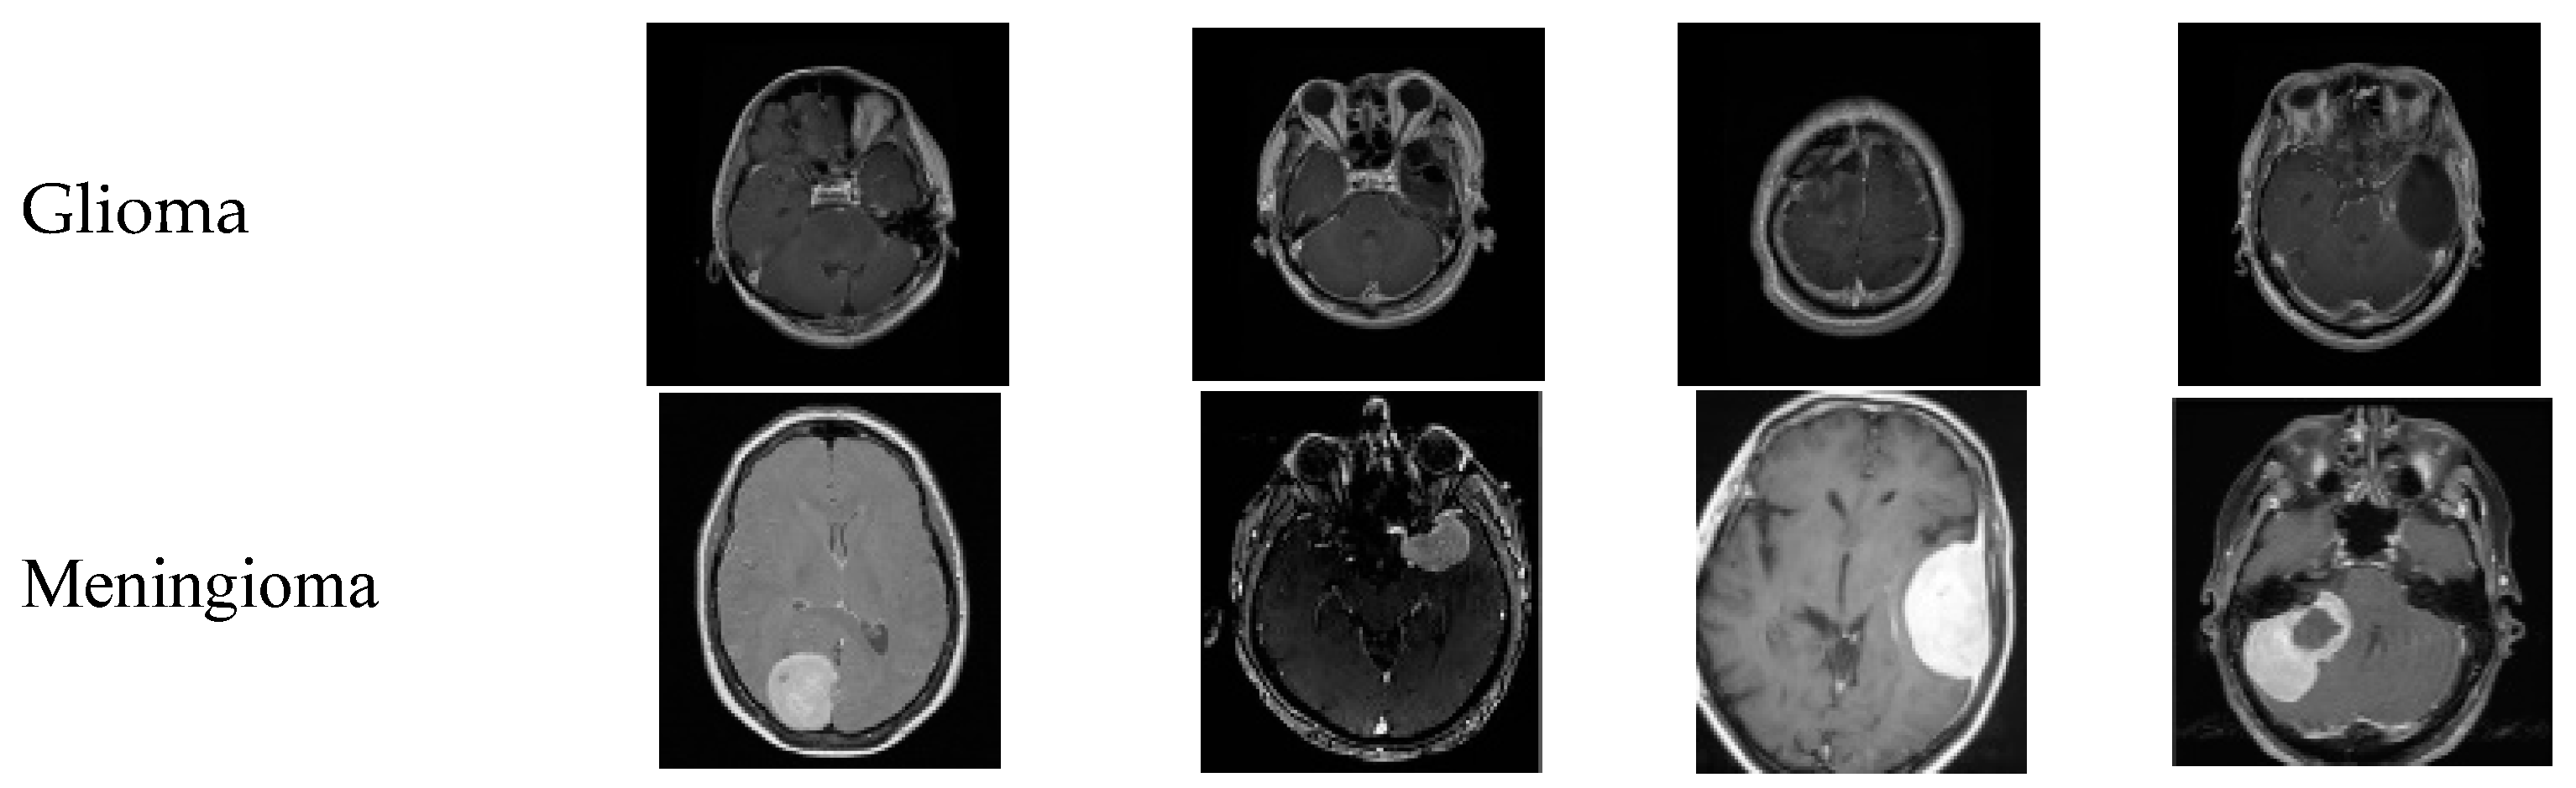

4.7. Dataserts Sample Images

Figure 4 shows the sample images of every class; the first row represents the sample MR images of class glioma, the second row has the meningioma class, the third row represents the pituitary class, and the fourth row represents the no tumor class. The images used in the no tumor class were obtained from the Br35H dataset. This dataset offers an extensive and varied collection of images to train and evaluate the models used in this study, enabling a more comprehensive analysis of the effectiveness of the models. Figure 4 displays a small selection of images from the dataset presented.

Figure 4. Sample images of the utilized dataset.

Brainsci 14 01178 g004aBrainsci 14 01178 g004b